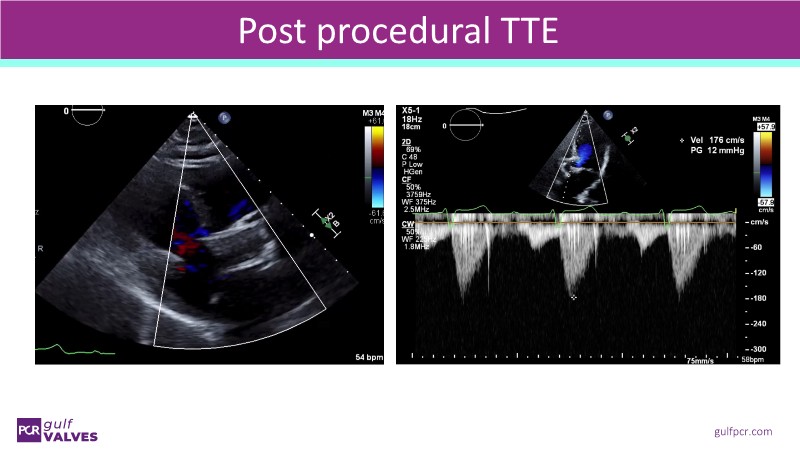

This session helps you anticipate and address complex scenarios such as mitral valve-in-valve, TAV-in-SAV, and valve-in-valve-in-valve procedures. Learn from expert case discussions that explore procedural strategies, technical challenges, and best practices to optimize outcomes in redo structural heart interventions.

- To anticipate and manage second valve scenarios with SAPIEN 3 Ultra RESILIA, including mitral valve-in-valve, TAV-in-SAV, and TAV-in-TAV

- To understand procedural strategies and challenges in complex redo scenarios using SAPIEN 3 Ultra RESILIA